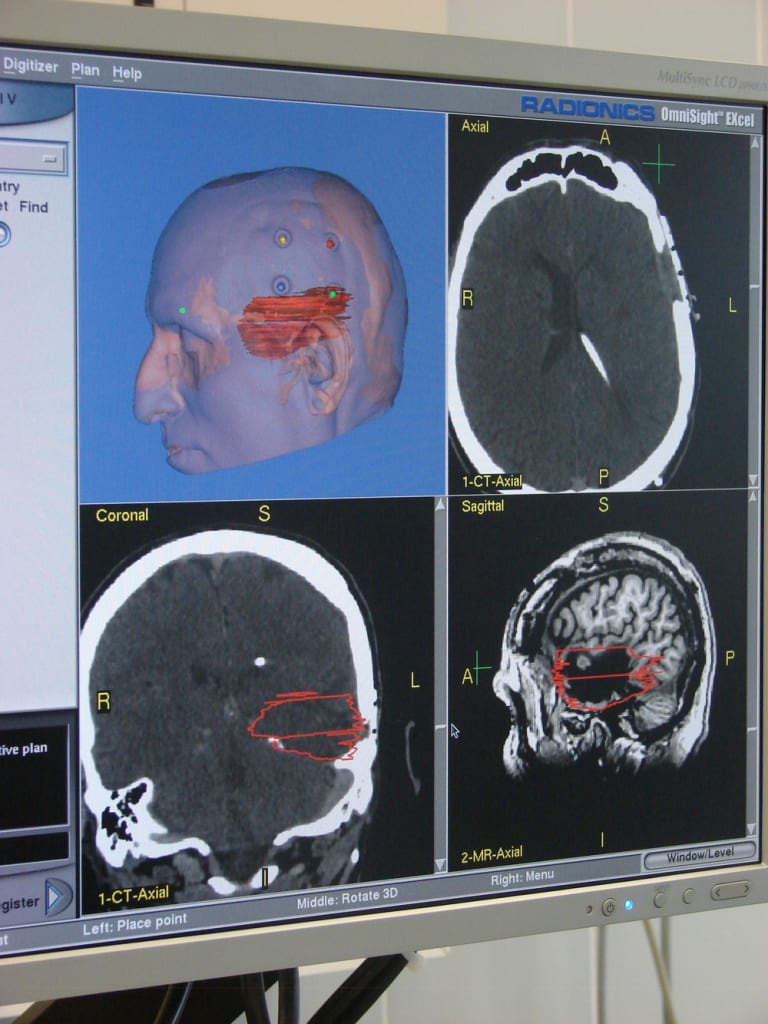

– Уже несколько десятилетий развивается еще одно перспективное направление в нейрохирургии – микрохирургия. Операции на мозге под микроскопом более эффективны и помогают избежать осложнений. А точность манипуляций помогает оценивать компьютер. Удаляемые опухоли могут располагаться очень близко к важным участкам мозга, и лишнее движение скальпеля может привести к травме. Поэтому специальные программы во время операции следят, не нарушит ли манипуляция функции нерва, отвечающего, например, за зрение или мимическую мускулатуру.